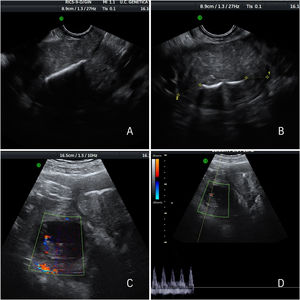

Dada la sospecha diagnóstica se decidió realizar una laparotomía exploradora, en la que se observó una masa intraovárica derecha de 8cm, sin signos de rotura, adherida a cara lateral uterina, siendo la trompa ipsilateral normal. El útero y el anejo izquierdo eran normales. Se realizó adhesiólisis de la masa ovárica, con rotura accidental de la misma y salida de feto (fig. 3). Dado el tamaño de la gestación, que abarcaba el ovario derecho en su totalidad, y la rotura de la masa, se desestimó la cirugía conservadora, optándose por salpingooforectomía derecha. El postoperatorio cursó favorablemente, con alta a las 72 h. El estudio anatomopatológico confirmó el diagnóstico de EO.

Imágenes de la cirugía en las que se observa salida incidental del feto del interior del ovario derecho al realizar adhesiólisis de la masa ovárica A), que se encuentra unida al útero por el ligamento útero ovárico A, B). En C) y D) se muestra la imagen macroscópica de feto y placenta, esta última implantada en la cara interna del ovario derecho.